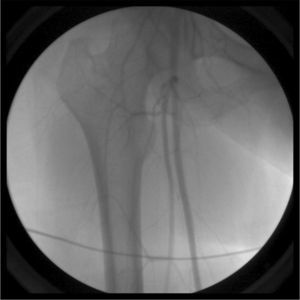

Se realizó una nueva arteriografía después del alta, con el objetivo de valorar la permeabilidad del lecho arterial que previamente se había mostrado ocluido. La arteriografía mostró arterias normales y se descartaron enfermedades arteriales asociadas (fig. 2). La angiorresonancia toracoabdominal permitió descartar vasculitis de otra etiología o trastorno del colágeno.